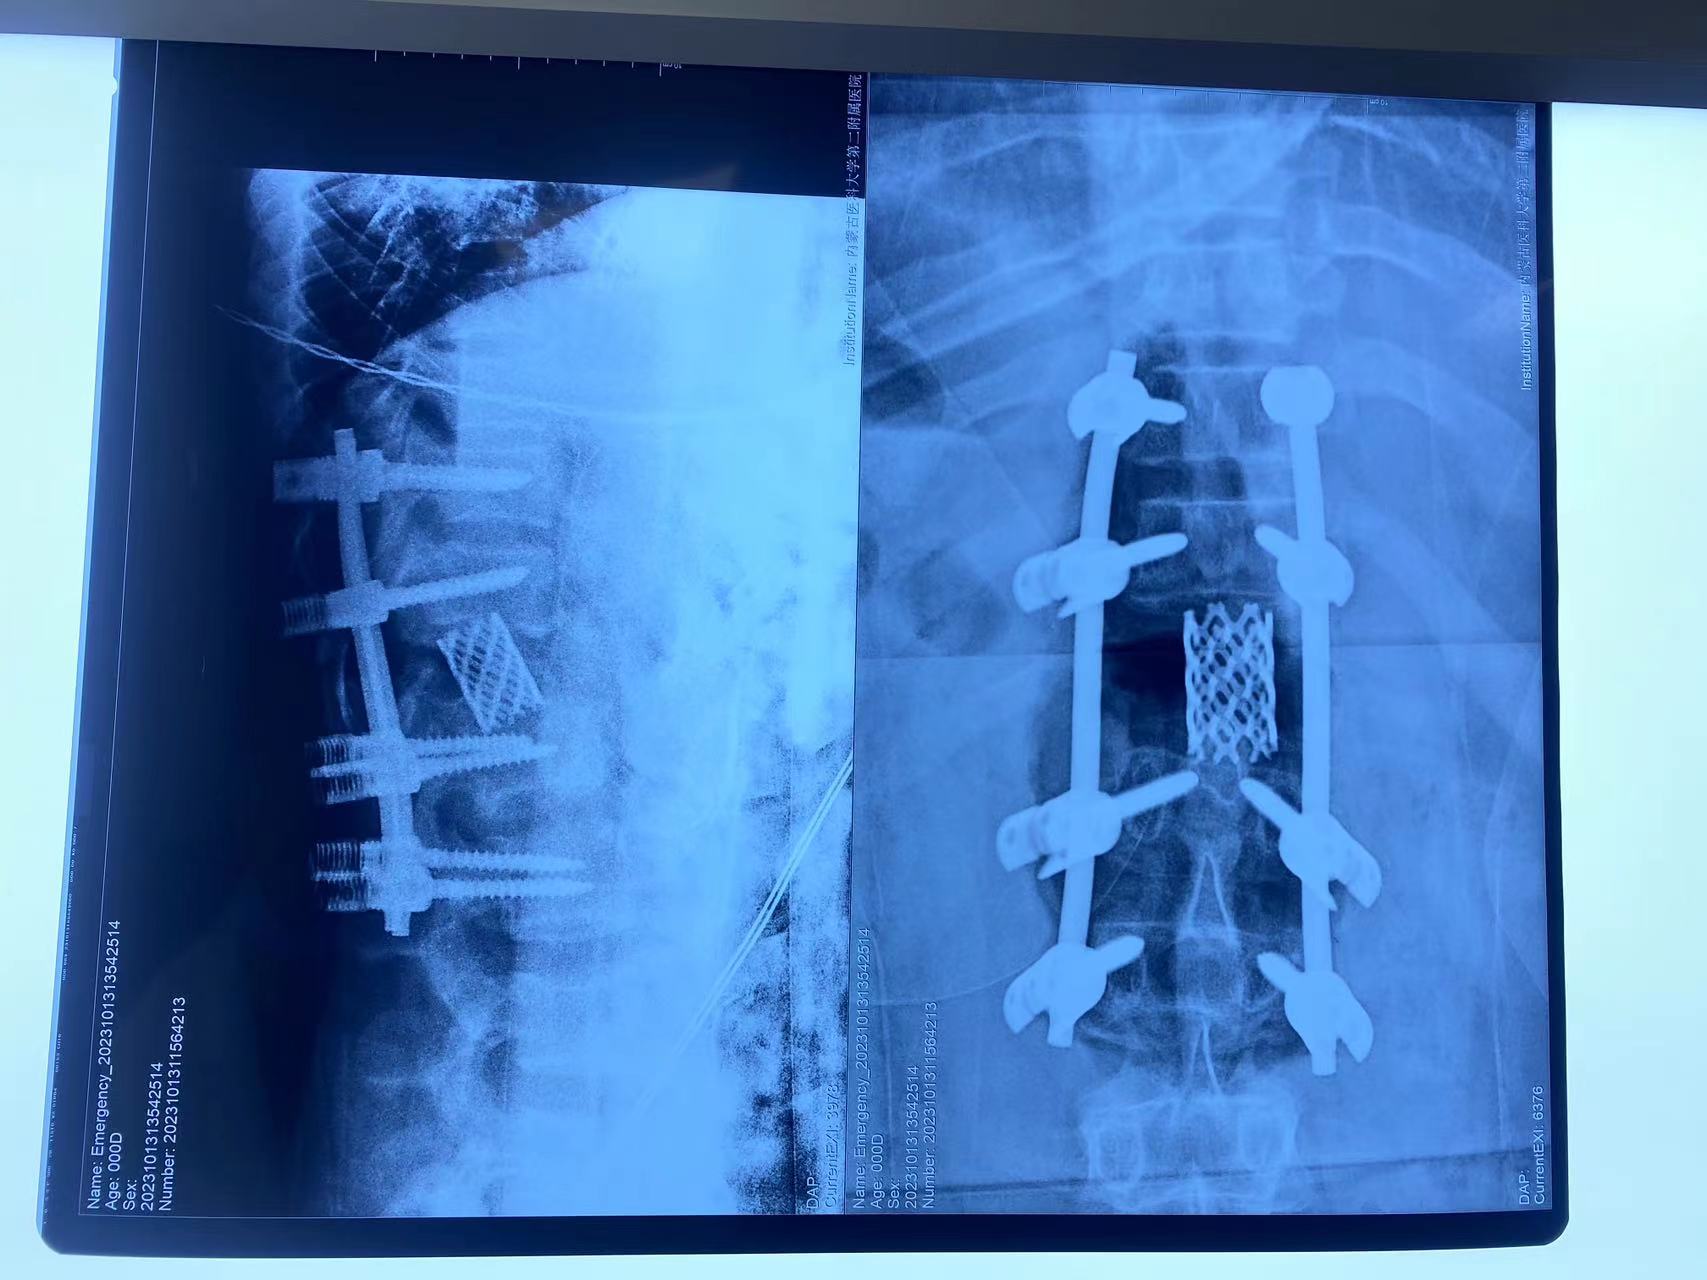

脊柱外科中心D区辛大奇、王东海、孙洪岩医疗团队完善患者术前检查后,明确诊断为胸12半椎体侧后凸畸形,经过积极与胡侦明教授沟通、讨论后,共同为患者制定手术方案,为患者施行先天性脊柱侧弯、半椎体侧后凸畸形截骨矫形+植骨融合内固定术。

胡侦明教授不远万里,亲临我院参加会诊并给予手术指导,最终在胡教授和我院医护团队的通力协作下,手术顺利完成,患者术后继续接受恢复治疗,状态良好,患者双下肢功能明显改善。近日,患者已顺利康复出院。